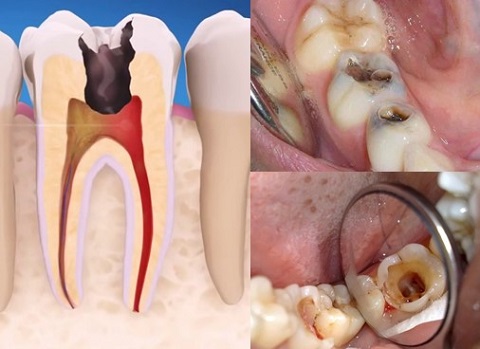

Viêm tủy răng là bệnh lý nha khoa phổ biến. Viêm tủy răng thường do sâu răng , do sang chấn, do viêm quanh răng… Triệu chứng của viêm tủy răng là đau nhức, buốt nhiều, đau lên đỉnh đầu, đặc biệt thử nóng lạnh sẽ rất buốt.

Sâu răng vào tủy là tình trạng khá phổ biến mà nhiều người đang gặp phải, cơn đau do sâu răng sẽ từ âm ỉ đến dữ dội. Sâu răng nếu không được điều trị có thể dẫn đến viêm tủy và gây ra nhiều biến chứng nguy hiểm cho sức khỏe. Vậy sâu răng viêm tủy có biểu hiện như thế nào và cách điều trị như thế nào cho hiệu quả thì mời các anh chị và các bạn cùng tìm hiểu trong bài viết dưới đây.